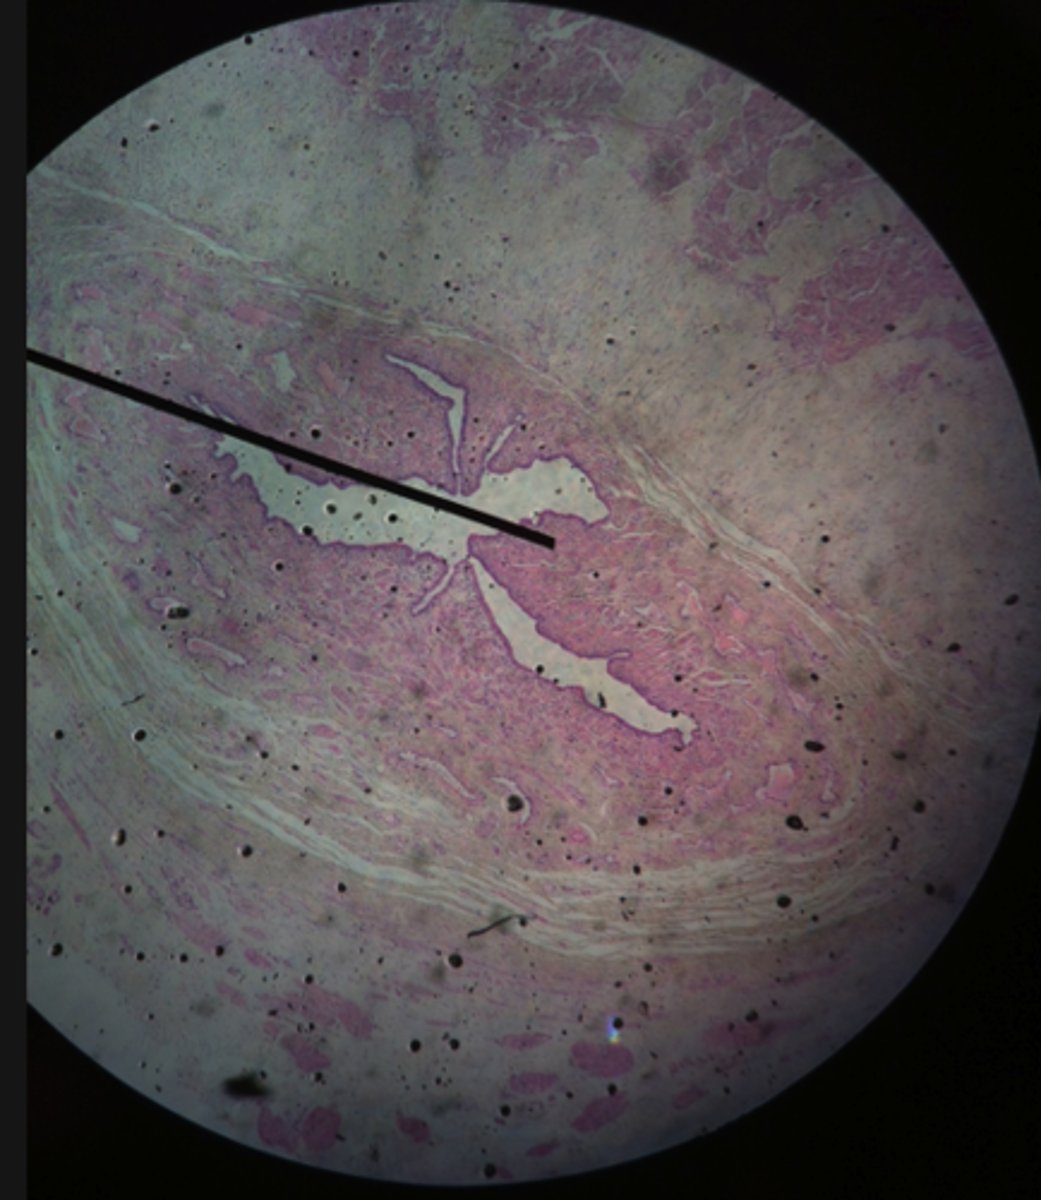

Spermatogenesis in Seminiferous Tubules